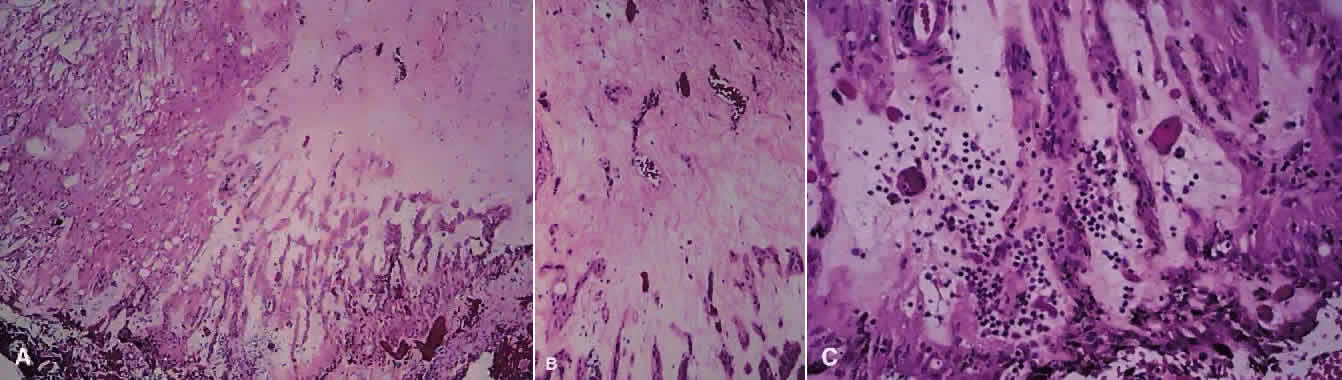

Much attention has been given to the histopathologic nature of the “snowbanks,” which has been studied by both light and electron microscopy.52,54,56–58 These fibrovascular-glial proliferations are found over the inferior pars plana and peripheral retina. They are composed of dense connective tissue derived from condensed, collapsed vitreous and often are vascularized. These vessels may reveal features of high endothelial venules (Fig. 8). Such endothelia are known to play a role in the homing of activated lymphocytes.54 The cellular elements of these membranes include fibroglial cells that are believed, based on their electron microscopic characteristics, to represent fibrous astrocytes, as well as nonpigmented ciliary epithelial cells, fibroblasts, and lymphocytes (Fig. 9).52–55,59,60 The vitreous is infiltrated by chronic inflammatory cells, and despite the nongranulomatous nature of the inflammatory component in the snowbanks, vitreous snowballs have been reported to consist of epithelioid cell granulomas.52

Fig. 8. Electron micrograph from eye with pars planitis (see also Fig. 9) showing collagen deposition and high endothelial venules (arrow).

Fig. 9. A. Photomicrograph of “snowbank” in patient with pars planitis showing a fibroglial mass with proliferated epithelial elements (hematoxylin and eosin; × 31). B. Higher magnification showing epithelial elements and glial proliferation (hematoxylin and eosin; × 80). C. Chronic inflammatory cell infiltrate in pars planitis (hematoxylin and eosin; × 200).